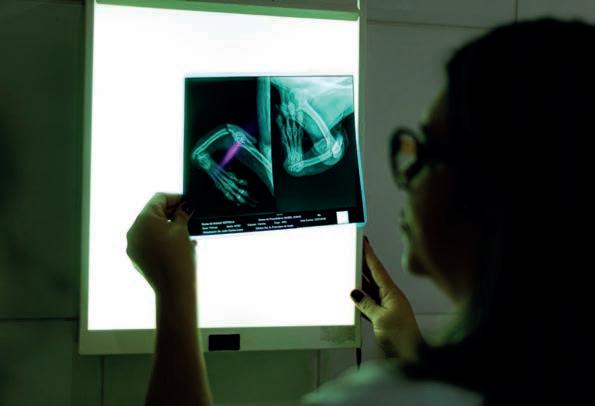

Alteração nas trompas pouco conhecida pode ser provocada porinfecções sexualmente transmissíveis

Uma condição chamada hidrossalpinge, que muitas vezes ocorre de forma silenciosa, pode deixar mulheres inférteis. A alteração ginecológica pouco conhecida provoca acúmulo de líquidos no interior da tuba uterina, que também é conhecida por trompas de falópio.

As tubas têm cerca de 10 centímetros e fazem a conexão do útero com os ovários, permitindo o transporte dos gametas para a fecundação, ou seja, o papel é essencial para possibilitar a gravidez.

Segundo o especialista em reprodução humana, João Guilherme Grassi, infecções podem atingir a estrutura, “Quando por algum motivo a tuba sofre inflamação pode se fechar e produzir acúmulo de liquido. O processo impossibilita que os gametas sejam levados, impedindo a gestação. É um problema muito sério, que pode passar despercebido por ser silencioso. Em casos provocados por Infecções Sexualmente Transmissíveis a mulher pode ter sintomas, como dor pélvica, corrimento vaginal fétido, dor durante as relações sexuais e até mesmo sangramentos anormais”.

Entre as causas mais frequentes estão as ISTs (principalmente clamídia) e endometriose. “No caso da endometriose a inflamação é causada pelo tecido endometrial implantado fora do local de origem. Caso a trompa seja atingida, ela pode ser obstruída e dilatada”, explica o médico. Para reduzir os impactos da doença na fertilidade, é importante que as mulheres façam exames com a finalidade de obter diagnóstico o mais rápido possível.

INFERTILIDADE

Um levantamento feito pela Organização Mundial de Saúde (OMS) aponta que 17,5% da população mundial adulta sofre de infertilidade, ou seja, 1 a cada 6 pessoas. A pesquisa foi baseada em resultados obtidos entre 1990 e 2021. A conclusão da OMS é de que é necessário aumentar o acesso aos cuidados de alta qualidade com o público feminino. O diagnóstico da infertilidade depende de avaliação médica criteriosa, no caso da hidrossalpinge, o diagnóstico pode ser feito por meio de uma ultrassonografia transvaginal.

Em casos de infertilidade com a presença de hidrossal-

Segundo o especialista, a infertilidade é uma possibilidade, mas caso apenas uma das trompas seja afetada, é possível engravidar de forma natural, mas com dificuldade

pinge é preciso realizar a cirurgia para a retirada da tuba obstruída.

POR MEIO DA FIV

De acordo com Grassi, ser acometida pela hidrossalpinge não significa que a gravidez será impossível. “A infertilidade é uma possibilidade, mas caso apenas uma das trompas seja afetada, é possível engravidar de forma natural, mas com dificuldade. A Fertilização In Vitro é uma alternativa para quando as estruturas estiverem comprometidas, tendo em vista que para fecundar o gameta, por meio da FIV, não é necessário ter o transporte feito na tuba”.